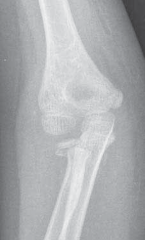

Chapter 8 Supracondylar Humeral Osteotomy for Correction of Cubitus Varus Yi-Meng Yen, Richard E. Bowen, and …

Chapter 3 Open Reduction and Internal Fixation of Fractures of the Medial Epicondyle Brian G. Smith and Krist…